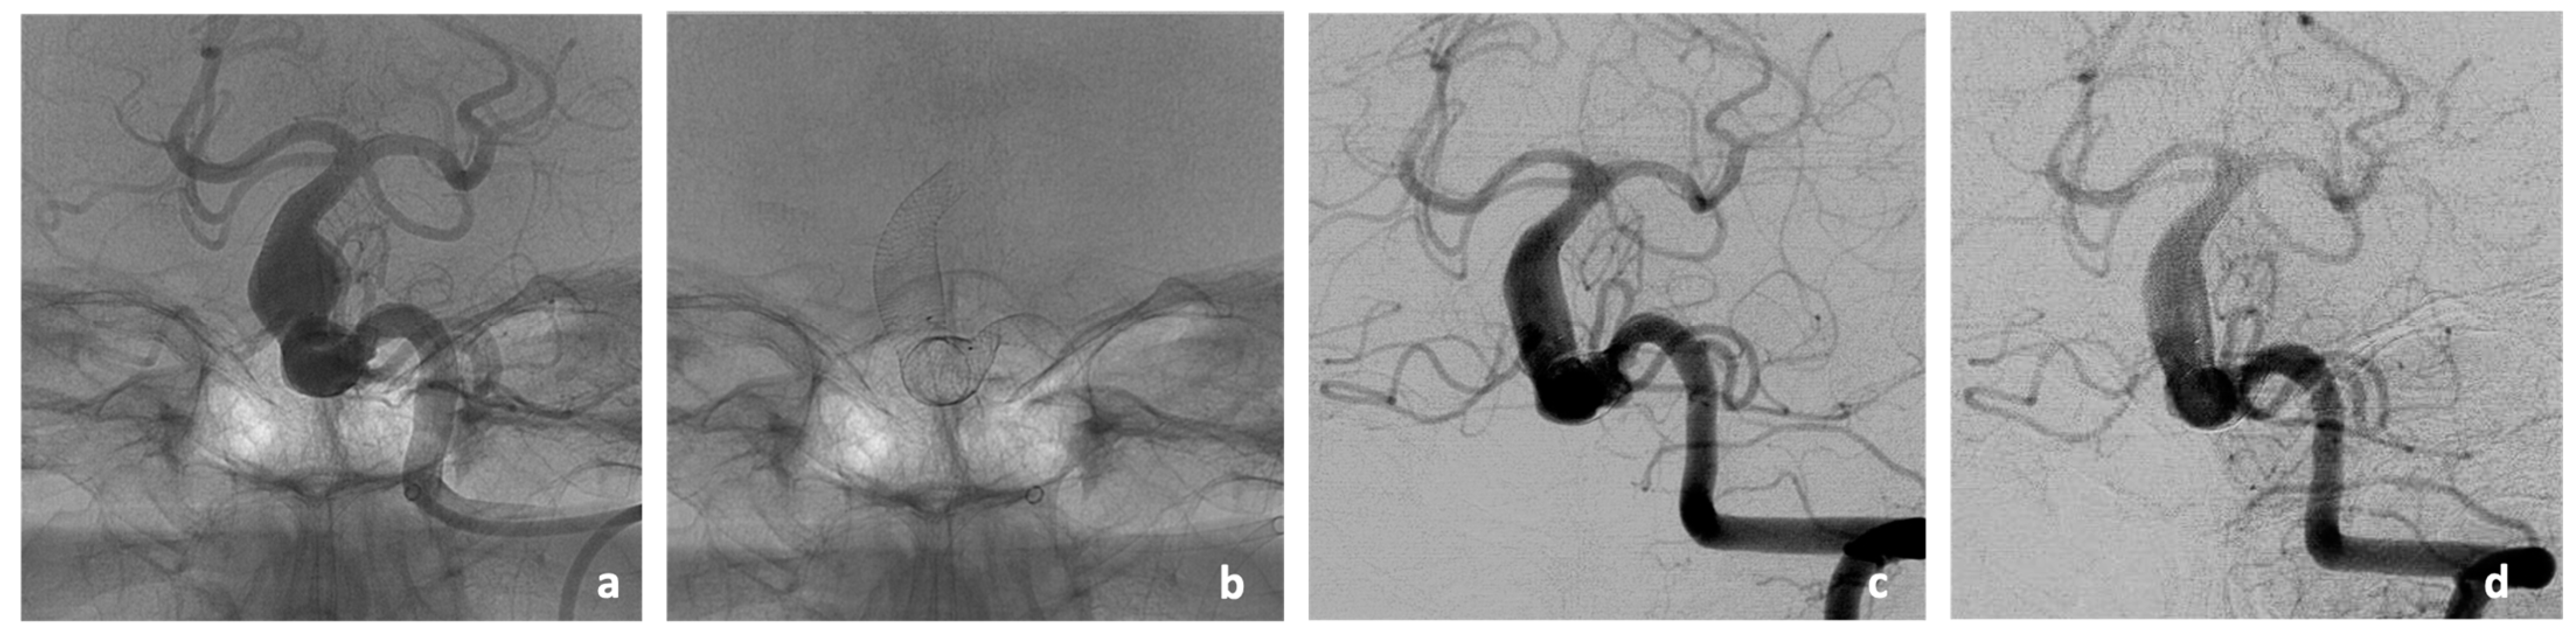

As an illustrative case of the vessel remodeling effect of the implanted stents, the DSA imaging of patient #2 in the three- and eight-months post-interventional course is given (Figure 2). In this case, the stent-covered aneurysm of the BA showed a significant reduction in size from the previous 11 × 11 mm to only 6 × 6 mm in the follow-up imaging at 3 months and stable size at follow-up imaging at 8 months. The follow-up of patient #5 showed a stable size of the stent-treated aneurysm at 3 months. Two patients died due to pathologies that were not associated with the intervention before follow-up imaging at 3 months could be performed (cardiac co-morbidities in patient #1 and pulmonary sepsis in patient #3). Furthermore, 3 months follow-up of patient #4 was still pending at the time of manuscript submission.

Figure 2. Imaging findings of Patient #2 during endovascular treatment with two Accero®-Rex-Stents (a,b) and three months later (c). After implantation of two Accero®-Rex-Stents in the BA (a,b), a clear remodeling of the previously existing aneurysm is already evident in the three-months course (c) with stable presentation in the eigth-months follow-up (d). Furthermore, there are no signs of in-stent-stenosis or thrombosis.